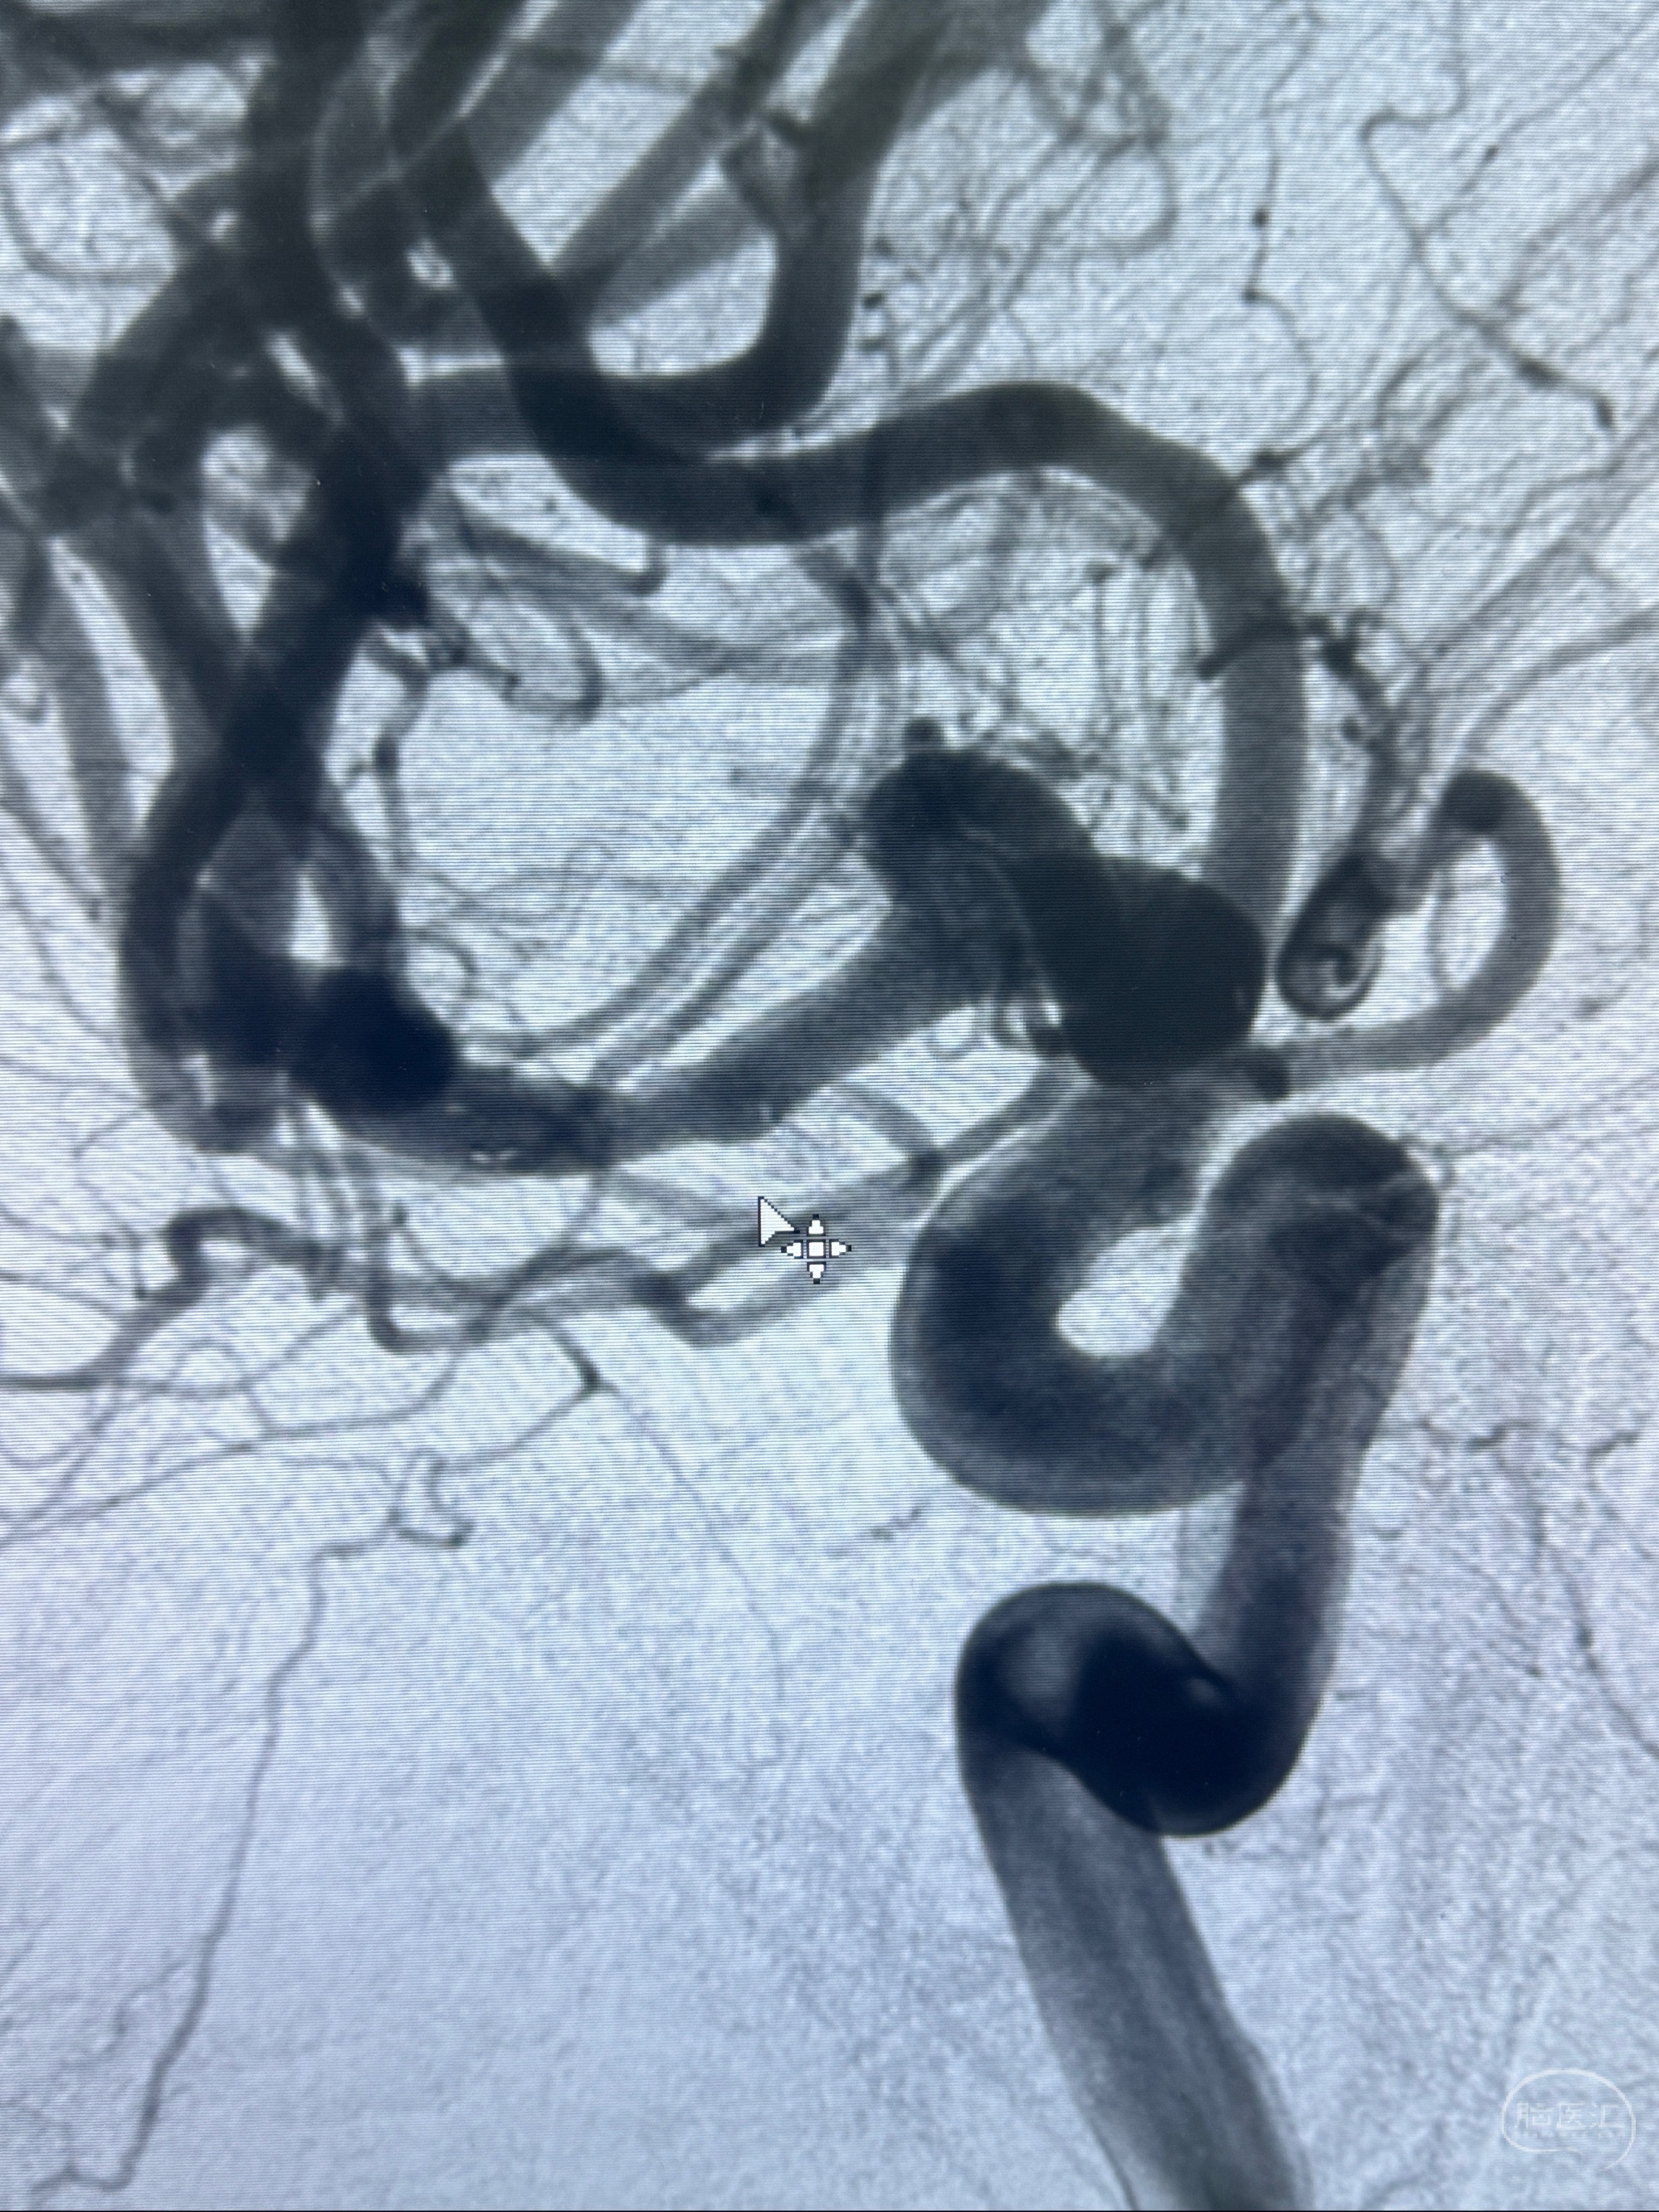

2023-11-24DSA:右侧大脑中动脉下干起始部动脉瘤,约2.3*2.5mm,形态规则

治疗策略:

- 随访?

- 夹闭?

- 单弹簧圈填塞?

- 支架辅助治疗?